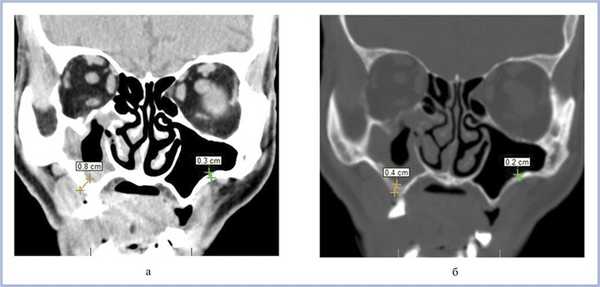

Воспалительные изменения слизистой оболочки верхнечелюстной пазухи, существующие в течение длительного времени, вовлекают в процесс костную стенку. На компьютерных томограммах отмечается утолщение костной стенки в костном режиме и появление «оптического эффекта» — уплотнение стенки в 1,5—3 раза за счет отека надкостницы — при просмотре в мягкотканом режиме (рис. 1, а, б) [9]. При одностороннем процессе, характерном для одонтогенного поражения, на контралатеральной интактной стороне такого эффекта не определяется.

Рис. 1. Рентгеновская компьютерная томограмма околоносовых пазух. Коронарная проекция: мягкотканное окно (а) и костное окно (б).